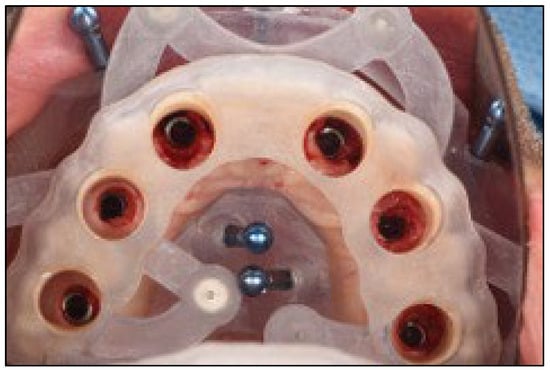

A stackable surgical guide system with magnetic retention was planned and fabricated. The guide set included a mucosa-supported base guide, an implant guide, and a multifunctional prosthetic verification guide. A flapless surgical approach was used. After base guide stabilization, the magnetic implant guide was sequentially positioned for each osteotomy. All six implants were placed according to the digital plan, achieving primary stability. Multi-unit abutments were installed to support immediate loading (Figure 8 and Figure 9).

Figure 9.

Multifunctional prosthetic verification guide—occlusal view—ensuring correct placement of the dental implants in relationship with the provisional restoration.

Stackable surgical guides, composed of modular components for adaptation, bone reduction, implant osteotomy, and prosthetic loading, minimize cumulative deviation in full-arch rehabilitation. As shown in this case and corroborated by the recent literature [,,,], these systems offer a highly accurate, efficient, and reproducible pathway for immediate loading. The magnet-based modular guide used here allowed for stable and flexible transitions between surgical stages, reducing chair time and increasing surgical confidence [,,,,].

Each component of the guide system was digitally fabricated using a comprehensive CAD/CAM protocol. The initial design workflow was performed in Real GUIDE Universal Open, with STL exports refined in Meshmixer (Autodesk, San Francisco, CA, USA). Retentive and anti-rotational features—including cylindrical guide housings and embedded neodymium magnets (5 × 1 mm)—were digitally incorporated to ensure precise repositioning and secure coupling of components.

The guides were oriented in PreForm (Formlabs, Somerville, MA, USA) and printed using a Formlabs 3B+ Dental SLA printer with biocompatible Surgical Guide Resin V1. Post-processing adhered strictly to manufacturer recommendations, including dual-stage isopropyl alcohol washes, air drying, and final light curing (30 min at 60 °C and 405 nm). Manual finishing was completed using rotary instruments, and magnet housings were cemented using dual-cure self-adhesive resin cement (Calibra Universal, Dentsply Sirona). Metal sleeves compatible with the implant system were press-fitted into the osteotomy channels to guide drilling and implant placement with maximum precision [,,,,].

The completed guides were sterilized via autoclave at 121 °C for 30 min, ensuring both biocompatibility and dimensional integrity. These stackable guides were designed for single use to maximize surgical precision and avoid cross-contamination.